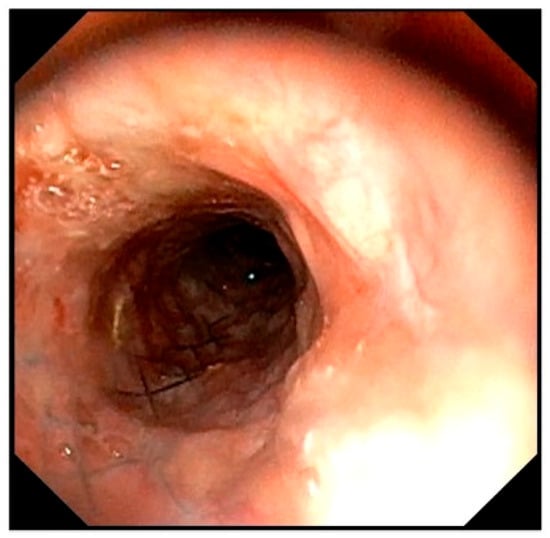

Tracheal stent fracture is a major complication of endoluminal tracheal stent (ELS) for canine tracheal collapse, and optimal management strategies remain unclear. A 4-year-old Yorkshire Terrier presented with respiratory distress caused by complete ELS fracture. Imaging and bronchoscopy revealed intraluminal protrusion of fractured stent segments, ventral tracheal cartilage invagination, and marked luminal deformation. A polypropylene linear prosthesis (PLLP) was selected as an external tracheal support. Its continuous band-like structure allowed broad and uniform reinforcement of the tracheal wall and redistribution of mechanical stress. PLLP placement successfully restored a near-normal tracheal contour and stabilized the fractured stent without introducing additional intraluminal material. Postoperative bronchoscopy confirmed improved tracheal patency, and no further deformation or stent damage was observed despite several months of altered airway dynamics associated with laryngeal paralysis. This case suggests that PLLP may represent a valid surgical option for managing tracheal stent fracture in dogs. Full article